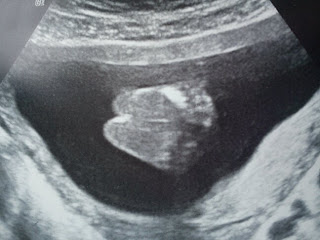

Thats me at exactly 12 weeks old.

This is when Mummy and Daddy found out that my Nuctual Fold was to large and this made me a high risk for Down's Syndrome. (1 in 5 Chance)

If u look at my scan picture you can see what i mean (its the big black bit on the back of my neck).